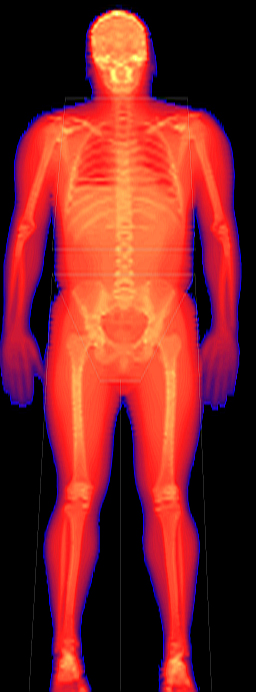

Norland utilizes automated technology to deliver efficient workflow and accurate studies without methodological error.

- Dynamic Filtration automatically adjusts the radiation dose based on tissue thickness, eliminating issues associated with saturation or starvation.

- Noise free X-ray detectors for optimized detection.